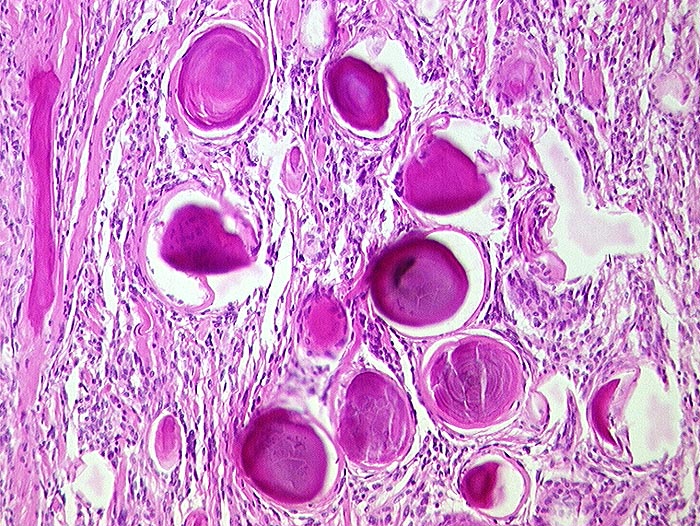

PathoPic – image database / PathoPic ID 255 - Psammomatöses Meningeom

Psammomatöses Meningeom

benigner Tumor

Meningen

Kugeliger Tumor im Bereich der Falx cerebri.

Histologie